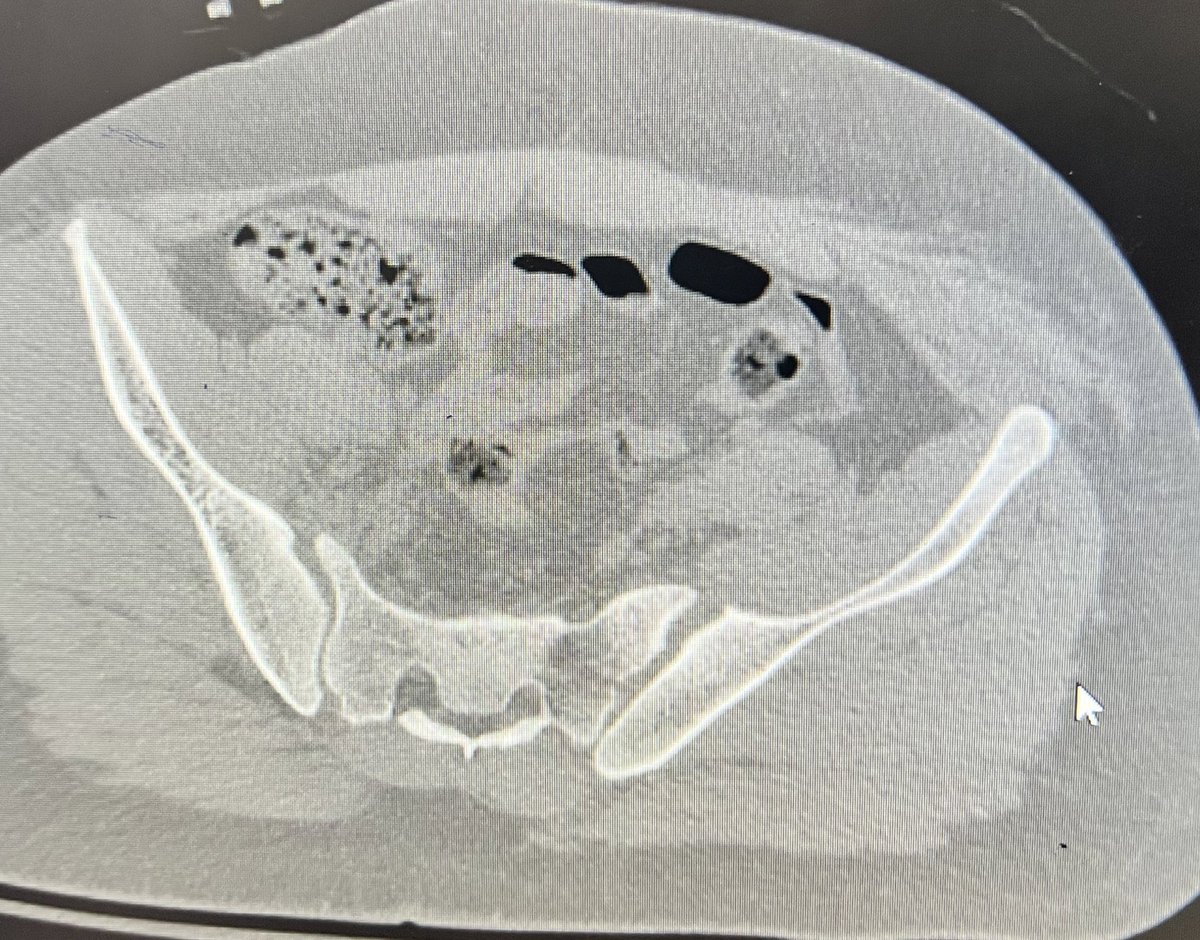

Day 2, case 2: infected femur non-union with shortening. Plan: debridement and irrigation with hardware removal. Circular external fixation for deformity correction and treatment of non-union. Will accept shortening for now.

@MirnaOchoa13 @RiceOlivia